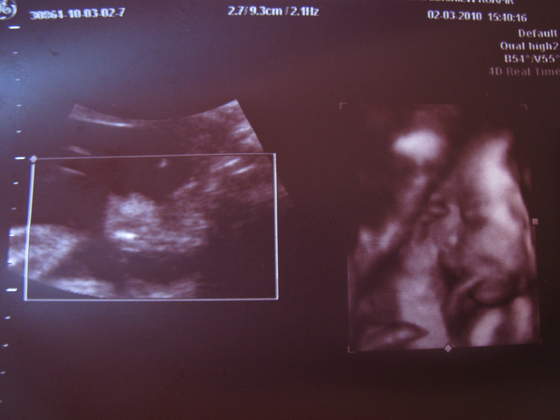

paula-śliczna duża babka i te murzyńskie usta ech!

ale lekarka mnie uspokoiłanadika wstydziosze z Natanka:-)Cudeńko z piękną wagąA co lekarz mówił na tą pępowinę?

Filipek![]()